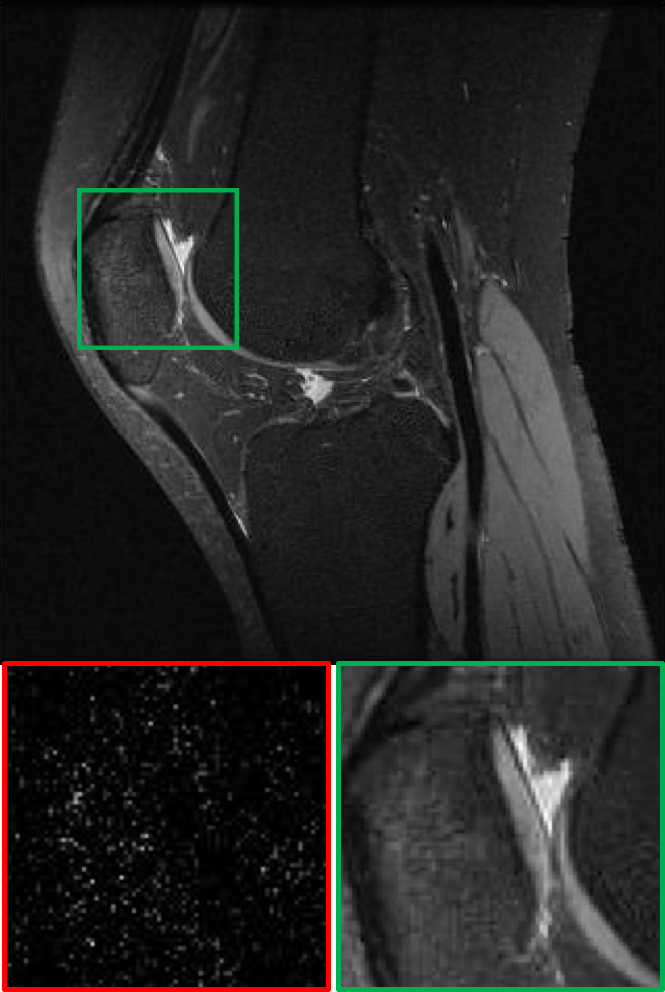

CS MR measurement matrix

LDAMP SURE was applied to CS-MRI reconstruction problem to demonstrate its generality and to show its performance on images that contain structures different from natural image dataset. We compared LDAMP SURE with state-of-the-art BM3D-AMP-MRI algorithm [16] for CS-MR image reconstruction along with TVAL3, BM3D-AMP, and dictionary learning method or DL-MRI [34]. Average image recovery PSNRs and run times are tabulated in Table 3. Figure 5 shows that our proposed method yielded state-of-the-art performance, close to the ground truth. The results reveal that proposed LDAMP SURE-T outperforms existing algorithms in all sampling ratios.

Ground truth

TVAL3

BM3D-AMP

DL-MRI

BM3D-AMP-MRI

LDAMP SURE-T